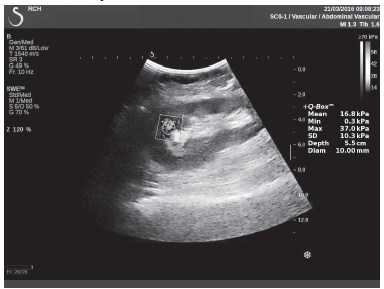

Клинический пример из первой группы. Пациент М., с хронической почечной недостаточностью. Трансплантация почки произведена от живого родственного донора. Трансплантат находится в правой подвздошной области. При нормальном функциональном состоянии трансплантата, показатели цветовой и спектральной допплерографии оценивались как удовлетворительные, с индексом резистентности не более 0,60 (рис. 1); показатели жесткости паренхимы почечного трансплантата при УЭСВ на различных участках составили от 20,05 до 29,18 кПа (рис. 2-4).

Рисунок 3. Исследование в режиме ультразвуковой эластографии сдвиговой волны у пациента М.: жесткость паренхимы в зоне верхнего полюса почечного трансплантата 21,4 кПа

Рисунок 4. Исследование в режиме ультразвуковой эластографии сдвиговой волны у пациента М.: жесткость паренхимы в зоне нижнего полюса почечного трансплантата 16,8 кПа